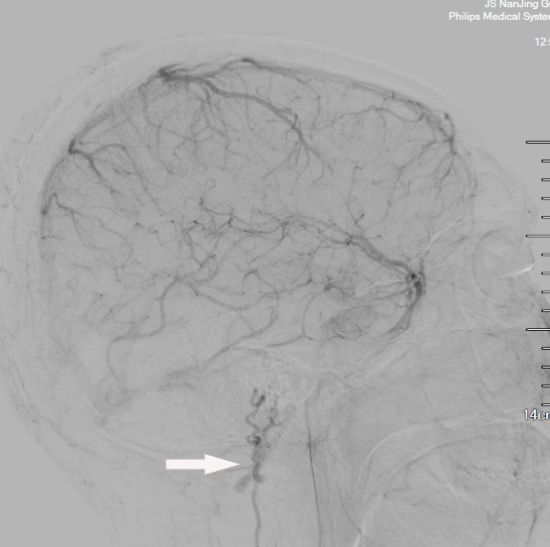

头颅MRA未见颅内异常血管,但头颅MRI-TOF像可见左侧天幕缘异常血管影(图2),CT薄层增强扫描见枕骨大孔区异常血管影(图3)。于2017年12月25日局麻下行全脑及全脊髓血管造影,脊髓血管造影未见异常,双侧椎动脉造影未见异常,最后行左侧颈内动脉造影示脑膜垂体干供血的天幕区硬脑膜动静脉瘘,瘘口位于岩骨中内1/3,直接经桥脑中脑侧静脉、扩张的延髓周围静脉向脊髓前静脉引流(图4)。造影诊断:左侧天幕区硬脑膜动静脉瘘。

图4. DSA血管造影

2018年01月22日行DSA复查示DAVF及回流静脉完全消失(图7)。

图7. 术后DSA复查